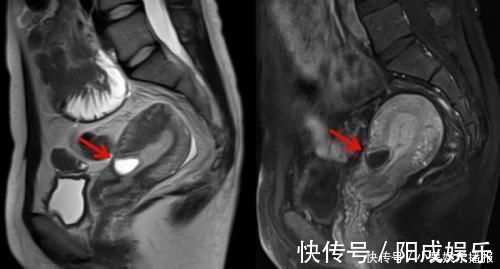

小倩随后便去医院检查,而后查出,小倩已经怀孕3个月左右了,并且是疤痕妊娠。当即,医生安排了手术,只是,在手术过程中还是遭遇了风险,为了保命,小倩被摘掉了子宫。